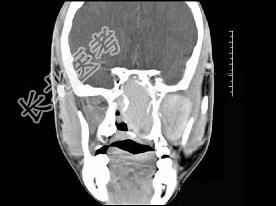

- 单项选择题男性,19岁, 左侧鼻腔反复出血一年余,CT、MRI扫描如图所示, 请选择最可能诊断 ( )

C、鼻咽部青年纤维血管瘤